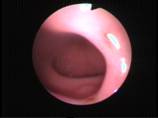

Torsion Testis (Pre and Per operative photo)